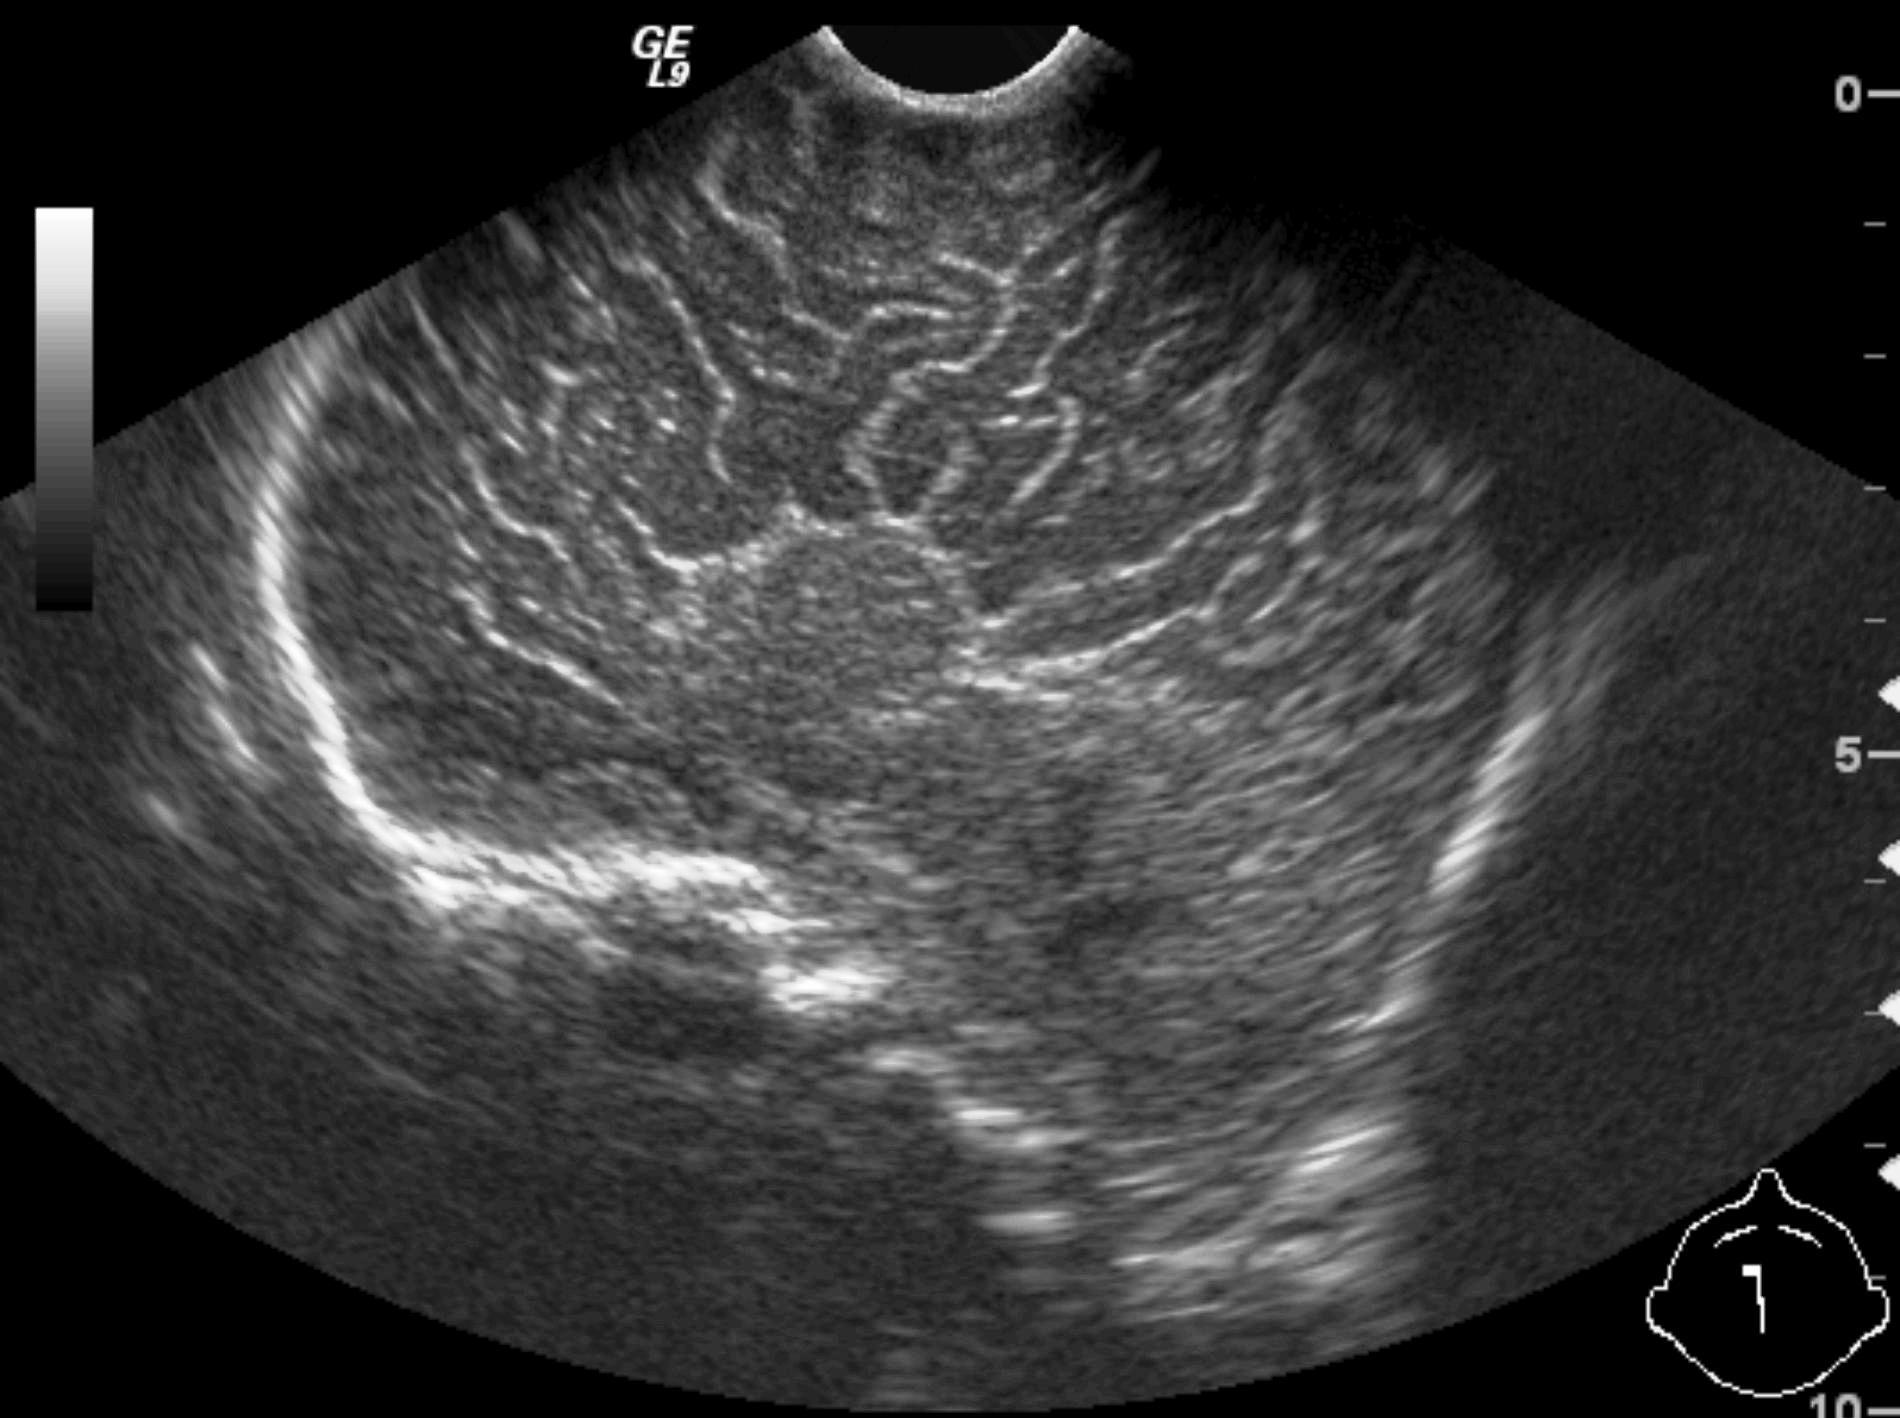

14. “Whirlpool” sign The mesentery and the superior mesenteric vein, as it coils around the superior mesenteric artery. Volvulus. US exam.

Image